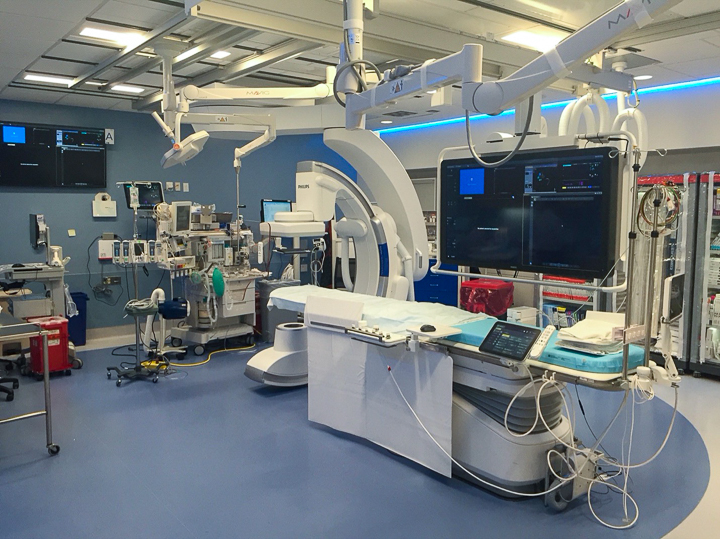

New IR Angiography Suite

The Department of Radiology and the Division of Interventional Radiology is proud to announce the opening of its new IR angiography suite and Vascular Access room at University campus. Having a second hybrid vascular and body IR suite will allow us to improve access to Interventional Radiology services and further expand our Interventional Radiology capabilities.

The Philips Azurion 7 C20 will allow us to provide top of the art diagnostic and therapeutic image guided procedures with lower radiation dose. Spacious rooms and special features will greatly improve patient satisfaction and will provide a safe environment for any complex intervention with ample space for anesthesiology.

Equipped with sophisticated advanced image-guidance systems and multi-imaging modalities, our physicians may now better visualize and treat patients with complicated diseases. This system includes technology to make this easier in both 2D and 3D with dose reduction technology. It is equipped with integrated Intravascular Ultrasound. Vessel Navigation guidance, 2D Vessel Perfusion, 3D roadmap and Vessel quantitative measurements are offered as well. Vessel Navigator allows reuse of 3D vascular anatomical information from existing CTA and MRA datasets as a 3D roadmap overlay on live X-ray images. With its sophisticated visualization, it provides an intuitive and continuous 3D roadmap to guide you through vasculature during the entire procedure. The system is connected to our PACS system allowing us to visualize previous diagnostic images inside the room.

Chromotherapy for the benefit of our patients under moderate sedation

As the clinician moves the system, the image beam automatically maintains alignment with the patient, allowing more consistent visualization and enabling them to keep their focus on the treatment. In addition, the room has ability to perform cone-beam XperCT, which will allow us to move some interventional procedures from one of the CT scanners on the first floor of University, further freeing-up capacity for diagnostic CT.

The room also is equipped with state-of-the-art video system for recording procedures and facilitating the education of our residents and fellows and performing live case demonstrations.

Stephan Wicky van Doyer, MD: “The performance, technology and quality of the new angio suite is absolutely fantastic. The room size allows multiple providers to feel comfortable and safe. It allows us to perform very challenging procedures in a safe and secure environment for the patient benefit. Different imaging guidance systems such as IVUS and Navigation, shorten the duration of the procedure and our patients also are exposed to a much lower radiation dose.”